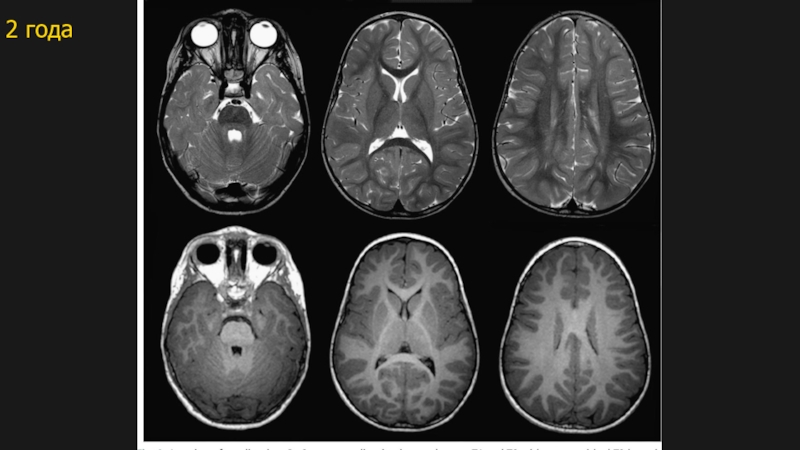

Слайд 142 года

2 года

12 мес2 года